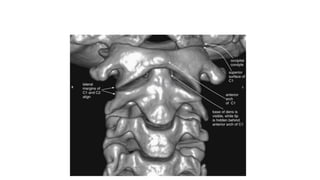

This three-dimensional CT model is oriented with the observer looking cephalad along the anterior

surface of the cervical spine. A series of holes perforating the transverse processes of each vertebra

can be seen—the transverse foramen.

This three-dimensional CTmodel is oriented with the observer looking cephalad along the anterior surface of the cervical spine. A series of holes perforating the transverse processes of each vertebra can be seen—the transverse foramen.